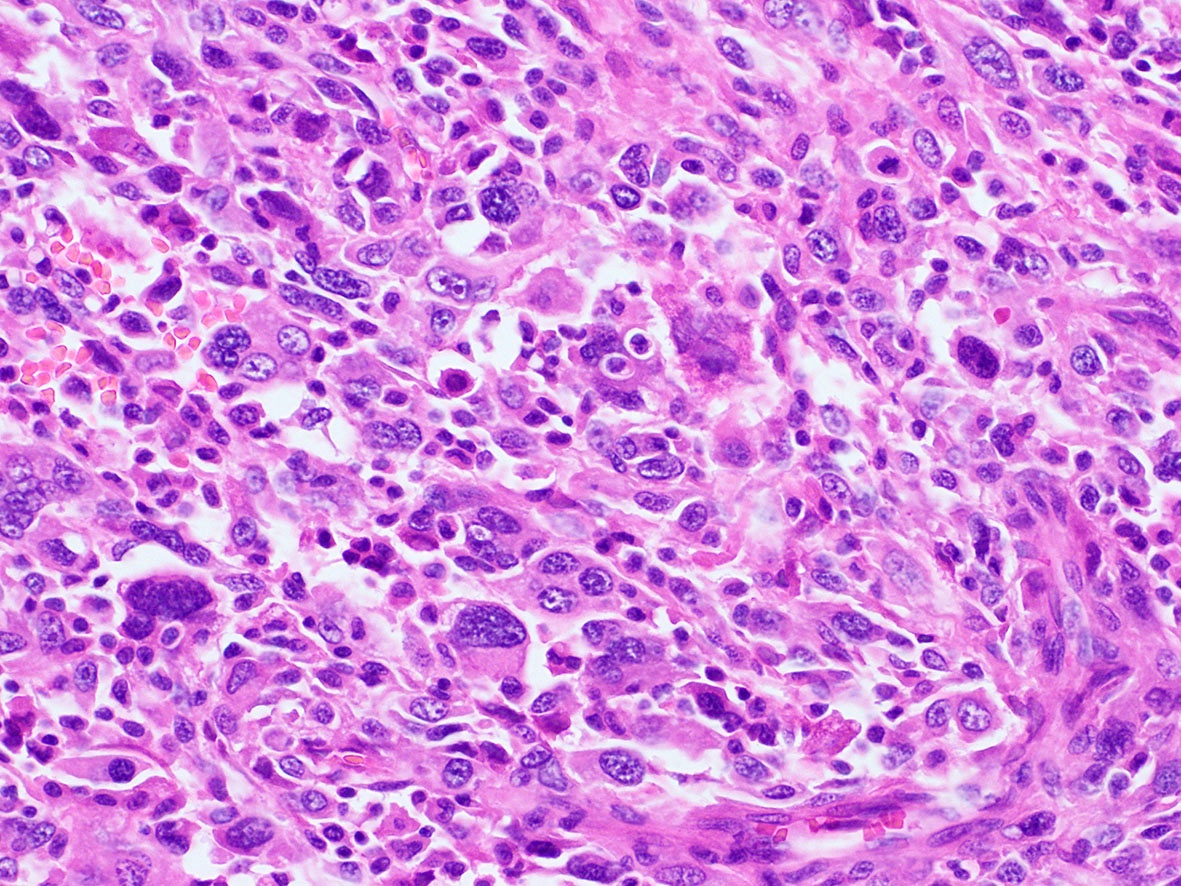

Microscopic (histologic) images

Contributed by A. Cristina Vargas, M.B.B.S., Ph.D., Patricia Guzman, M.D., Fiona Bonar, M.B.B.Ch., Alison Cheah, M.B.B.S. and Martin Jones, M.B.B.S.

Positive staining - disease

- ALK overexpression as a result of gene translocations / fusions:

- ALK+ anaplastic large cell lymphoma (ALCL) (Science 1994;263:1281, Semin Diagn Pathol 2020;37:57)